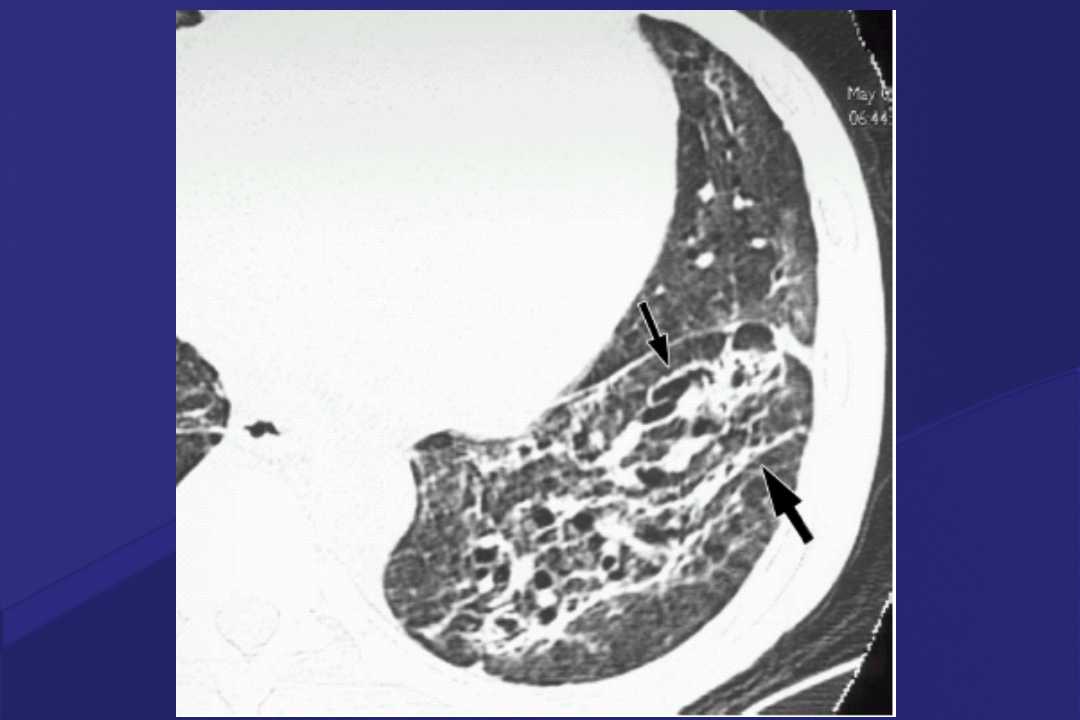

血液疾病患者肺部并发症影像学表现